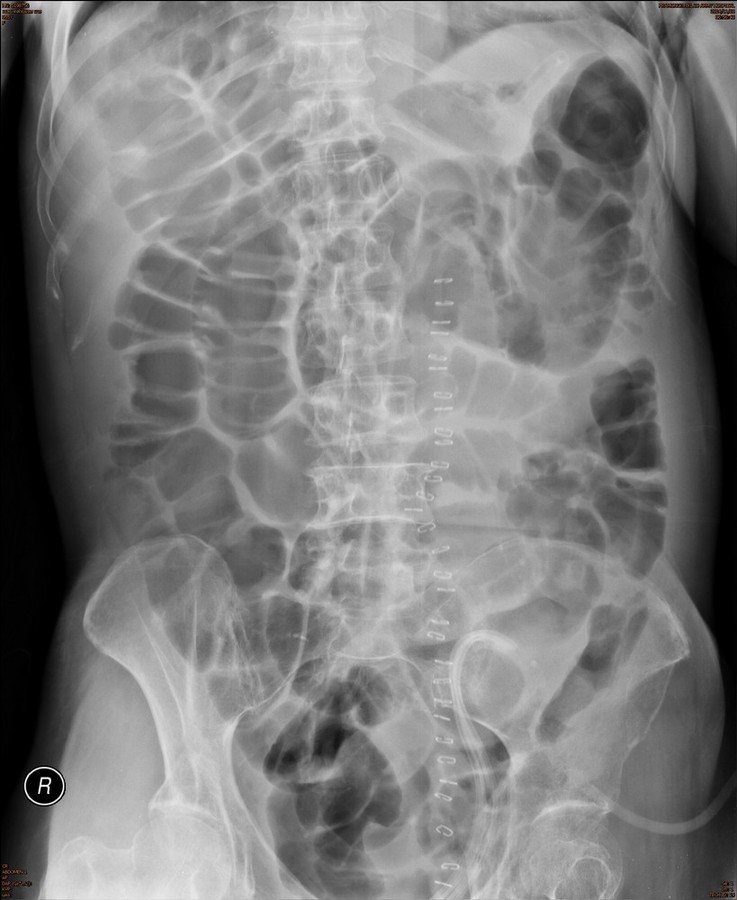

History :  A 50-year-old man with abdominal distension.

Answer : C .Small and large bowel dilatation

• This film shows abdominal suture clips on the skin, corresponding with S/P abdominal surgery

• Small and large bowel dilatation in this case, due to post operative ileus

• Ileus is a term used for aperistaltic bowel not caused by a mechanical obstruction

• Multiple loops of gas filled bowel projected centrally over the abdomen

• There are multiple loops of gas filled bowel projected centrally over the abdomen

• This patient had prolonged non-colicky abdominal pain following a abdominal surgery recovery was spontaneous